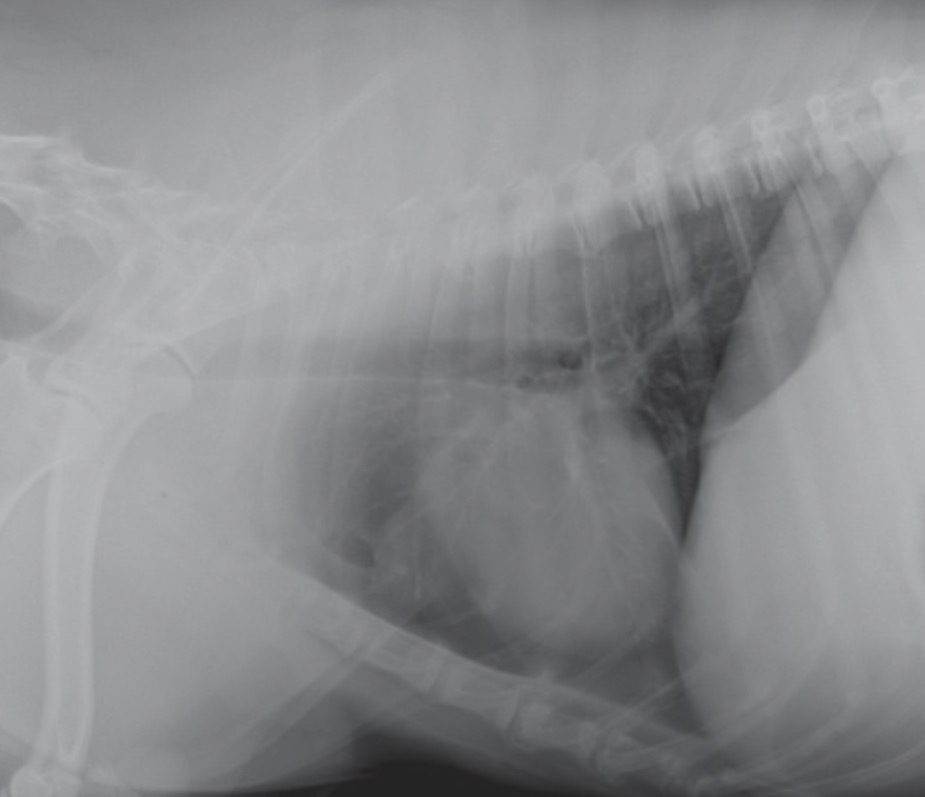

Hi, I am the lucky and grateful owner of my beautiful boy Tarzan, we have recently received the horrible news that our baby has been diagnosed with a tumour in his stomach, we first noticed symptoms a few months ago when he stopped eating his food and would instead go out into the garden and chew on rocks or grass to force himself to throw up, at this time our family was going through some very tough times financially with rent and needing to cover costs for our kids and couldn’t afford the trip to the vet until around 3 weeks ago.

Since his diagnosis we have only seen his condition get worse and we know that if we don’t do anything to help treat him soon he is just going to live in so much pain and suffering.